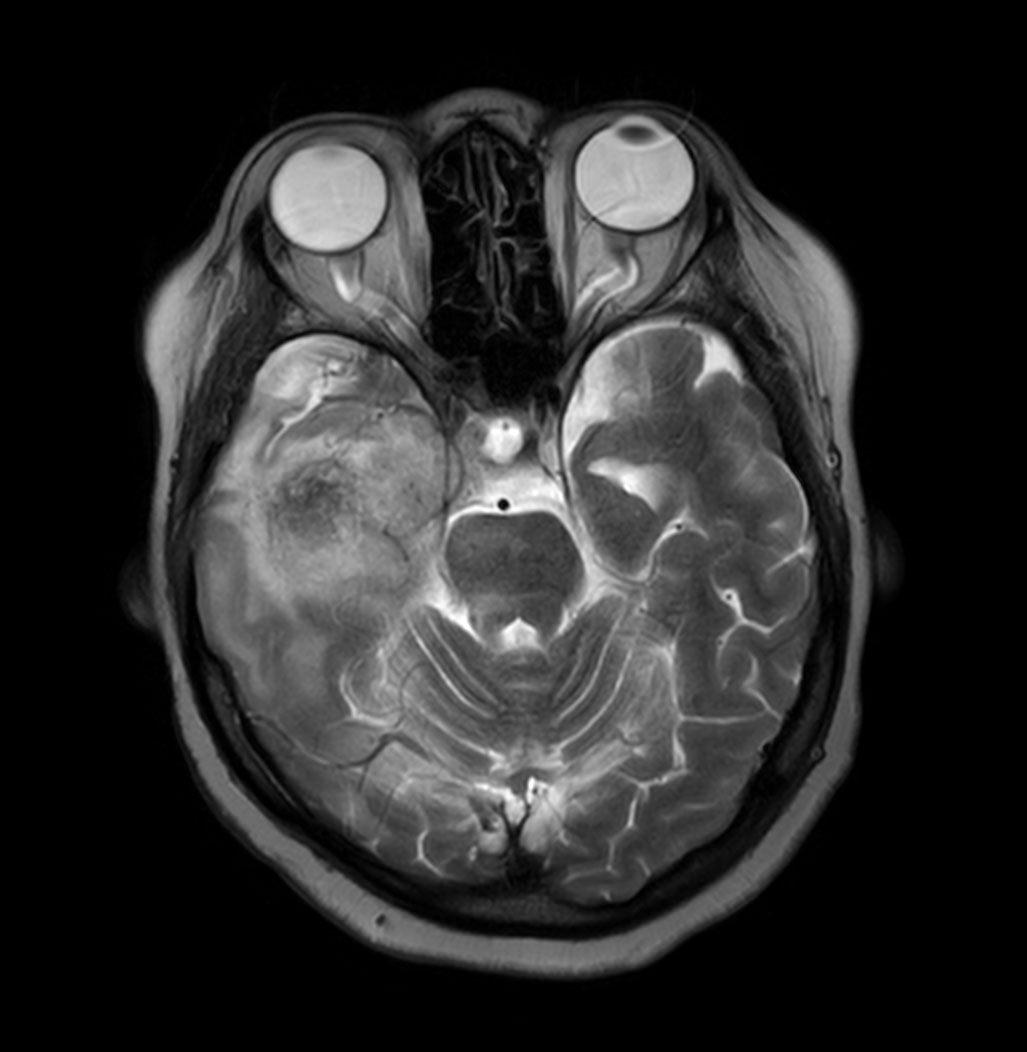

Brain astrocytoma post radiotherapy, incl. 3D APT

Patient with a history of astrocytoma. MRI scan requested post radiotherapy treatment. Diagnosis: Recurrent neoplastic disease.

Axial T2w TSE